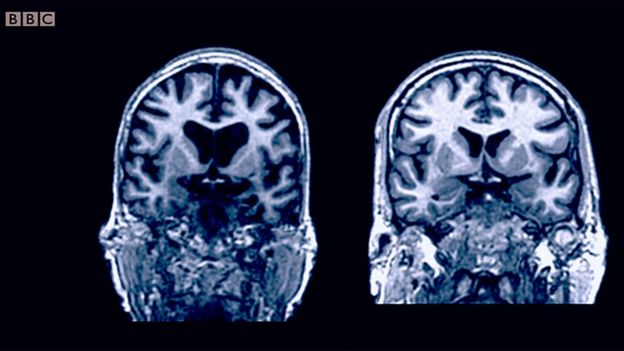

É provável que sim. Veja como a massa cerebral é diferente entre as duas pessoas que aparecem na imagem abaixo. Ambas têm a mesma idade.

“Não parece ser algo inevitável: o nível de atrofia e danos à substância branca varia de pessoa para pessoa. O que queremos entender é que fatores no estilo de vida ou no comportamento fazem diferença”, diz Gow.